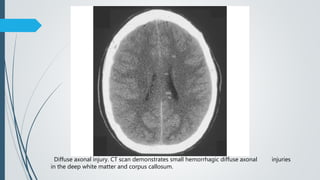

Diffuse axonal injury. CT scan demonstrates small hemorrhagic diffuse axonal injuries

in the deep white matter and corpus callosum.

NECT

 Not very sensitive

 Often normal (50-80%)

 >30% with negative CT have positive MR.

 Nonhemorrhagic : small , hypodense foci

 Hemorrhagic : small hyperdense foci (20-50%)

 Size – punctate to 15 mm

 They typically become more evident over the first few days as oedema

develops around them. They may be associated with significant and

disproportionate cerebral swelling.